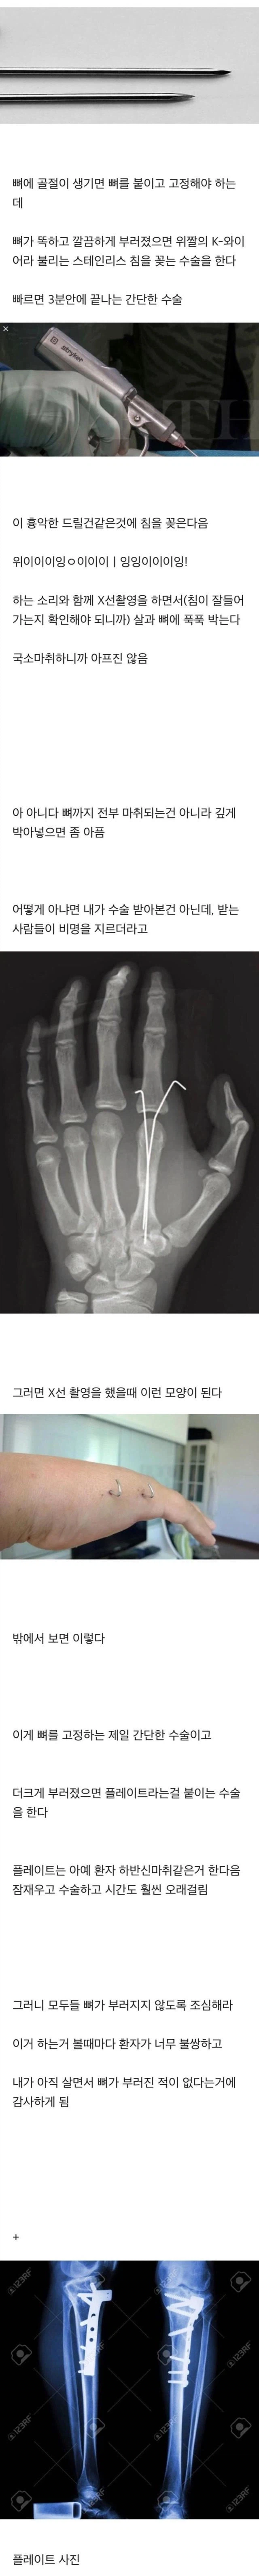

뼈가 부러지기 전에는 의외로 모르는 사실 Anonymous | 2026.03.07 21:12 | 조회 32 https://qquing.net/bbs/board.php?bo_table=humor&wr_id=1843173 주소 복사 이전글 다음글 랜덤 만화 목록 본문 추천 0 비추천 0